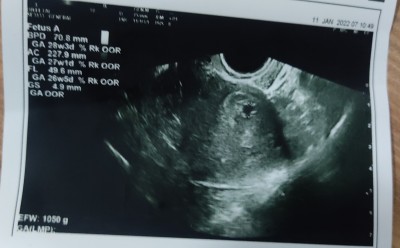

son adet tarihine göre 7+3 beta 2029 ve bugün keseyi bu şekilde gördük sizce normal mi ilk gebelik

Gebelik haftası

7+3

Bence normal biraz geç döllenme olmuş sanırım.